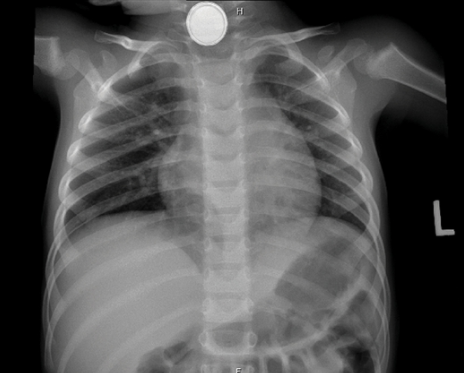

여러 전자제품에서 수은 건전지의 사용이 증가함에 따라, 불행히도 이를 삼켜서 내원하는 아이들이 종종 있다. 수은 건전지는 소화관 점막에 부식성 손상, 전기 화상, 압력 손상을 일으켜 매우 위험한 이물질이다. 직경이 클수록 손상이 더 심하고 빠르게 진행되며, 4시간 이내에 식도 전 층에 화상을 일으켜 부식성 식도염, 천공, 종격동염 등을 일으킬 수 있다. 수은 건전지를 삼켰을 경우에는 금식 여부에 관계없이 가능하다면 2시간 이내에 내시경으로 제거해야 한다. 동전과 생김새가 비슷하지만, X-ray 상 수은 건전지는 가장 자리에 이중 음영이 관찰되는 점에서 구별이 가능하다.